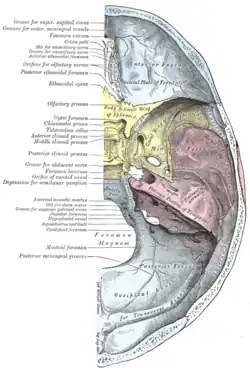

Base do crânio. Superfície superior.

Base do crânio. Superfície superior. -